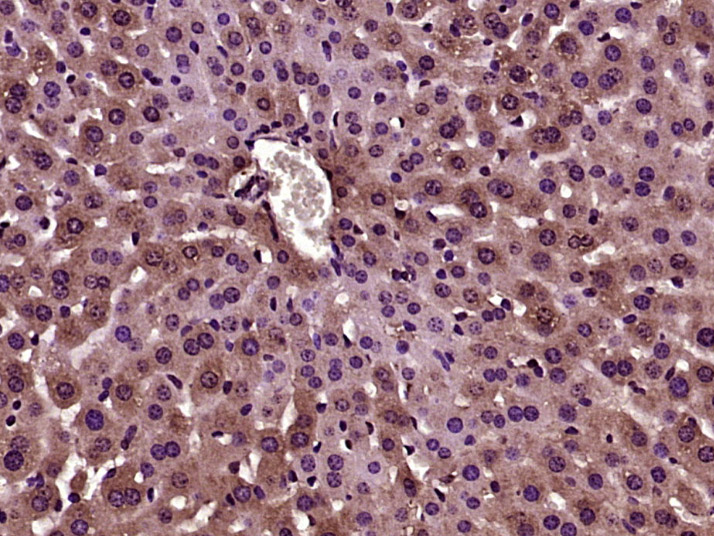

| 英文名称 | PFKFB1 Rabbit pAb |

| 中文名称 | 果糖-2,6-二磷酸酶1/磷酸果糖激酶2抗体 |

| 产品应用 | IHC-P=1:100-500, IHC-F=1:100-500, IF=1:100-500 Not yet tested in other applications. |

| 组织特异性 | Liver. |

| 背景资料 | PFKFB1 belongs to the family of bifunctional 6-phosphofructo-2-kinase:fructose-2,6-biphosphatase enzymes. It forms a homodimer that is involved in both the synthesis and degradation of fructose 2,6-bisphosphate. The activity of this enzyme is thought to regulate glucose homeostasis. |

| {IHC-P} | {1:100-500} |